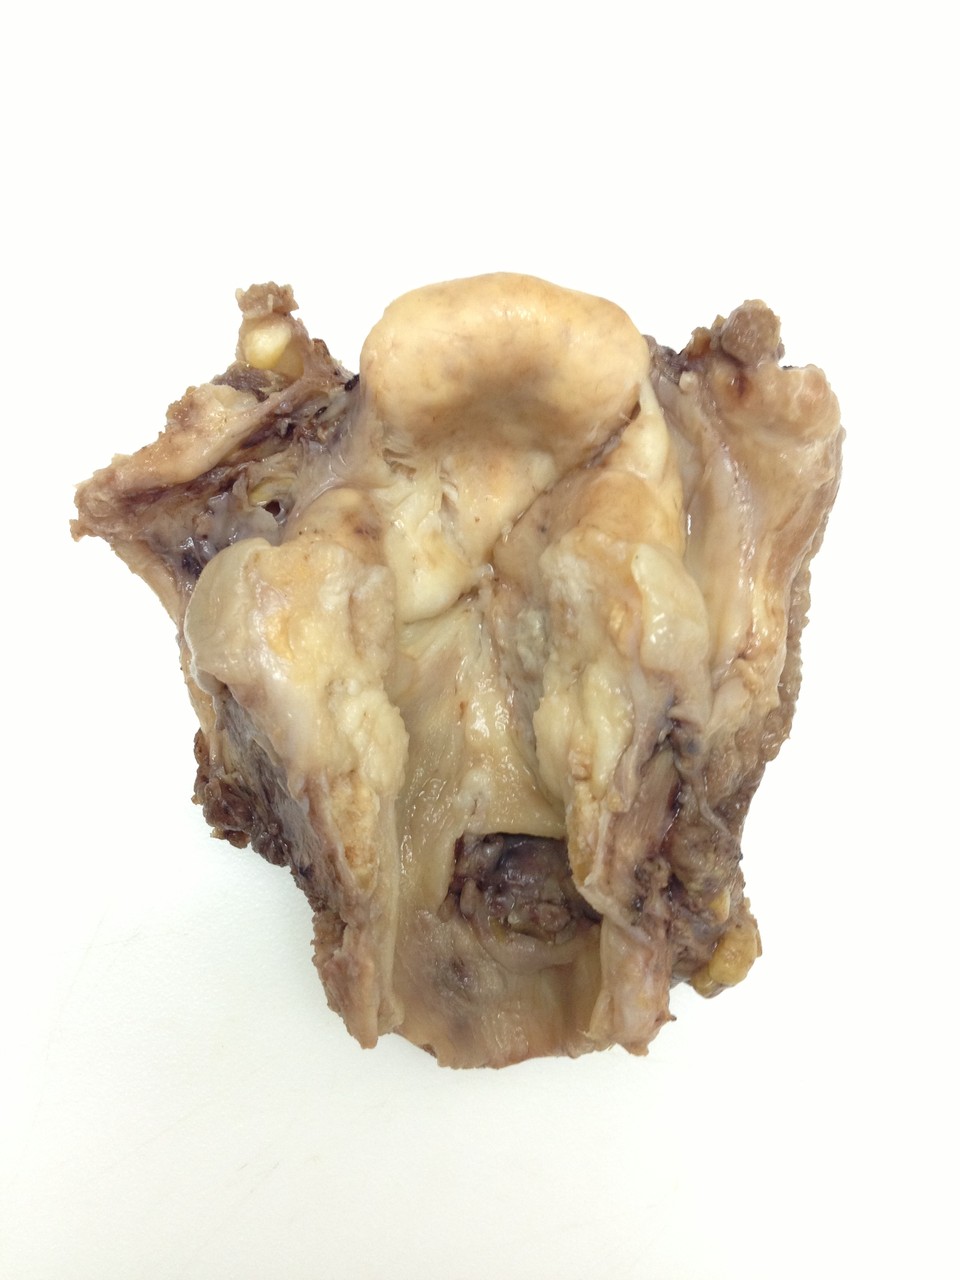

Patología Molecular

El diagnóstico sobre muestras de tejidos y líquidos corporales en plena era de la medicina del futuro, está basado en la integración de técnicas y conocimientos diferentes.

Hoy más que nunca es importante integrar una buena historia clínica con un correcto estudio de imagen y una buena morfología que además puede estar apoyada con proceso especiales complementarios relacionados con la Inmunología, Biología Molecular y Citogenética, generando así un estudio integral conocido como Patología Molecular.